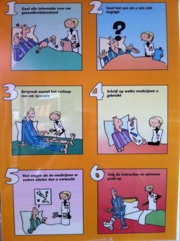

De operatie-assistente is langs geweest en heeft in het kort verteld wat mij morgen te wachten staat.

De operatie-assistente is langs geweest en heeft in het kort verteld wat mij morgen te wachten staat.Ik heb daarna met mijn vrouw Grietje een klein rondje UMCG gelopen.Mijn vrouw is na de wandeling afgereisd naar Leeuwarden.

Ik heb nu even tijd om een vragenlijst in te vullen.De arts, dr. Wapstra die mij morgenvroeg gaat opereren, kwam ook even kennismaken.

Het was een leuk gesprek, ik zie er na uit……..Ik word morgen om 11:30 uur (ijs- en weder dienende) geopereerd.